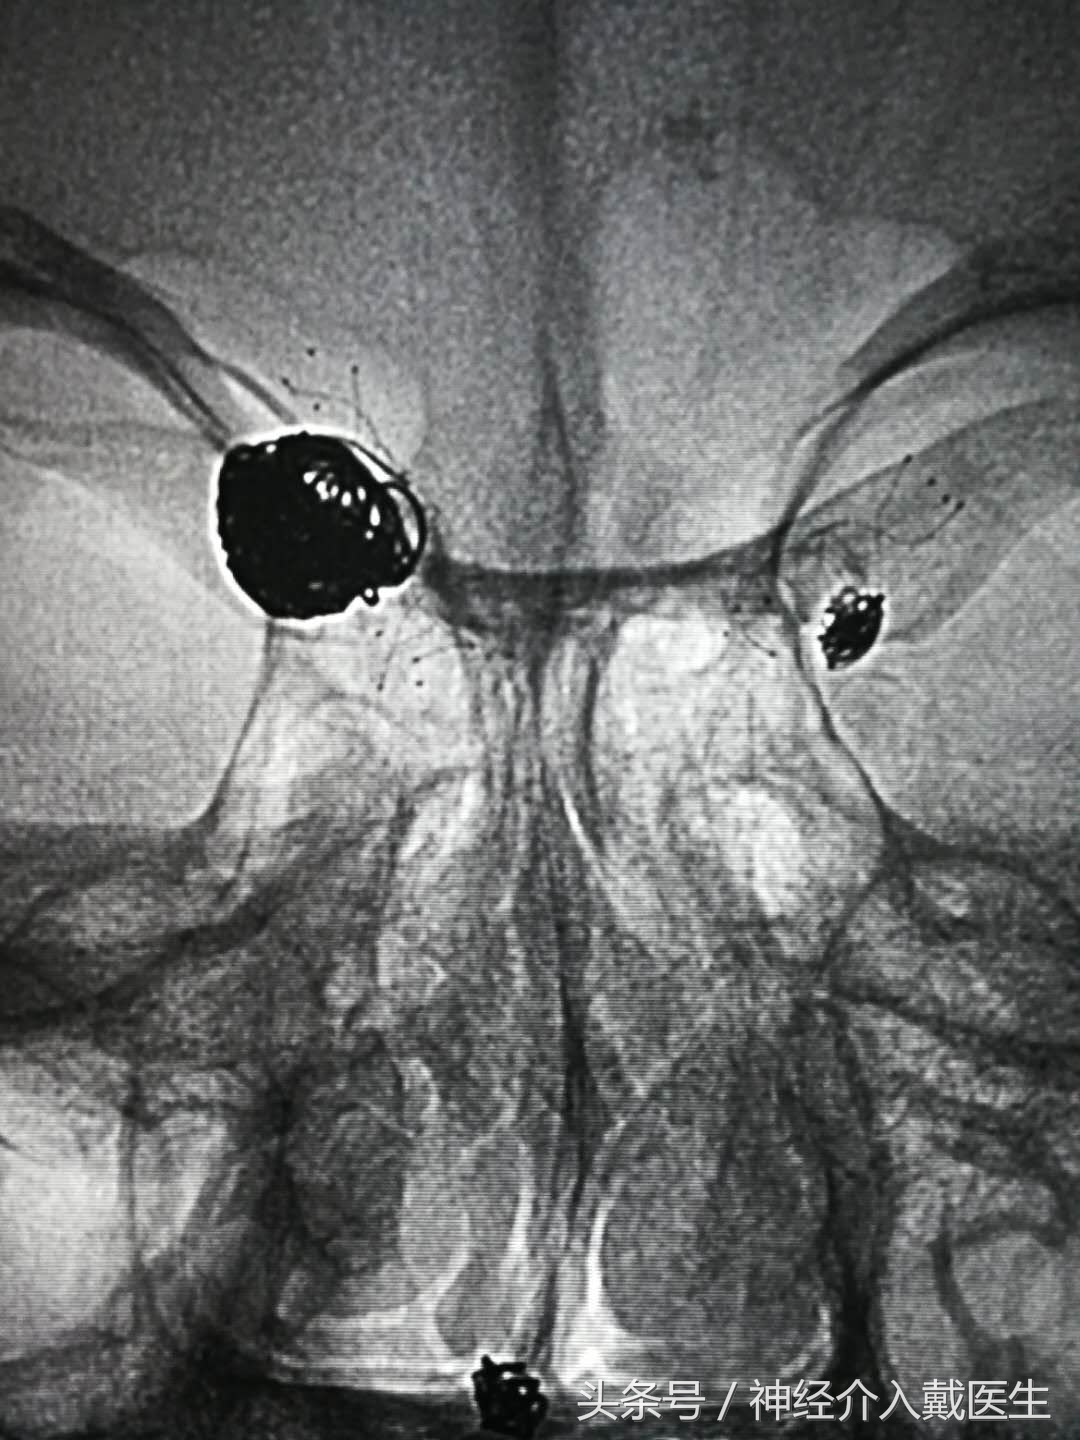

对于宽颈,梭形复杂的动脉瘤,如果开颅手术,也是很有难度的,介入栓塞有时可以相对简单,使用支架可以防止弹簧圈突入载瘤动脉,使动脉瘤介入治疗成为可能,

支架辅助弹簧圈动脉瘤栓塞术大大提高了介入治疗的适用症,特别对于超宽颈,夹层,梭形动脉瘤,大大改善了动脉瘤治疗的长期疗效,支架网丝的脚手架作用促进了动脉瘤颈部位的内皮细胞的生长覆盖,促进了瘤颈部位的解剖愈合,另外,支架也改变了载瘤动脉的形态和角度,引起血流动力学的变化而促进动脉瘤的长期愈合,支架的运用改变了动脉瘤治疗的理念,